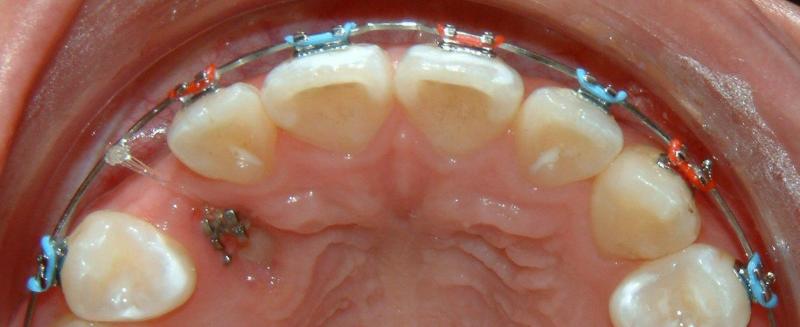

Without surgical exposure and forced eruption, there was practically very little progress with natural eruption of the upper right canine for nearly 3 years (not shown). With the surgical exposure (laser -> no bleeding) and forced eruption, the progress can be seen almost immediately - within a month (Fig. 9). After 2 months, the crown is more visible: part of the crown can be seen clearly (Fig. 10). After 8 months, the crown is moved into the position (Fig. 11). With additional 3 months, the crown is relatively well leveled and aligned (Fig. 12). It takes longer to treat the palatally impacted canine.

Fig. 11 Forced eruption, 8 months after surgical exposure (progress)

© Copyright 2007-2014, Vu Orthodontics. All rights reserved.